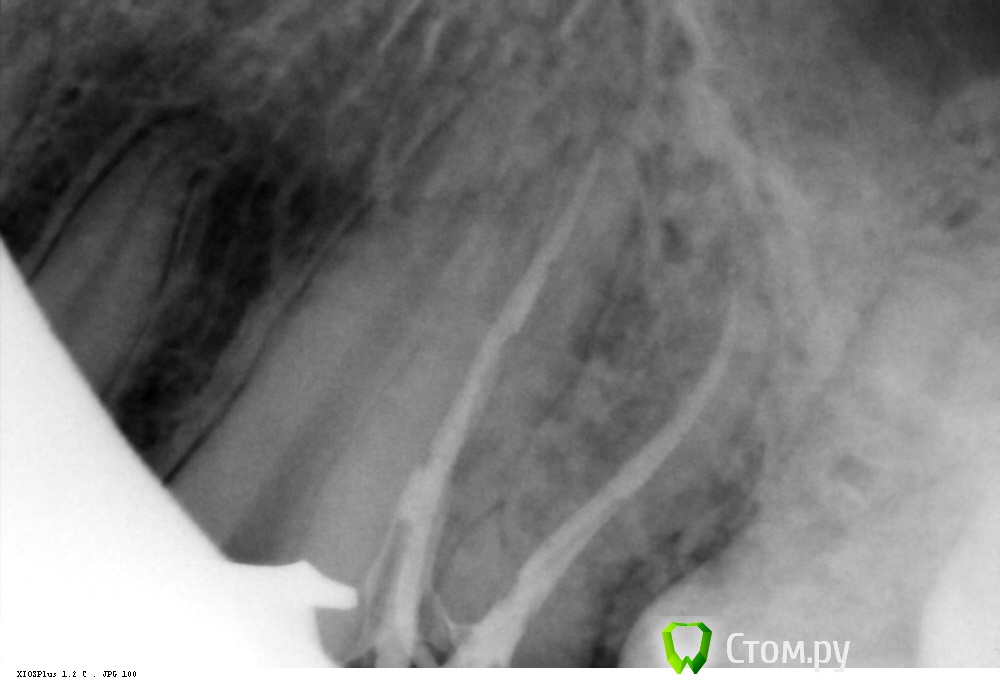

Shaid Опубликовано 9 февраля, 2014 Автор Поделиться Опубликовано 9 февраля, 2014 Первый сломанный Протейпер.Ds: хронический пульпит 46. После ковровой 25 ломанул S1 в мезиально-щечном. Обошел ручными кое-как) Отломок заклинил на стенке канала. Подцепляю H-файлом, не идет. Ультразвуком тоже пытался.Коллеги, если попробовать клеем и он заклеит обходной путь к апексу, его можно будет потом пройти файлами?Посоветуйте! Ссылка на комментарий

Kolchanov Опубликовано 9 февраля, 2014 Поделиться Опубликовано 9 февраля, 2014 Оставь его в покое, раз обходится. Он в перешейке, пусть там и остается. Будешь долбить, потом он в апекс упадет и вообще фиг достанешь. А в дистальном что раскорячилось? Ссылка на комментарий

Shaid Опубликовано 9 февраля, 2014 Автор Поделиться Опубликовано 9 февраля, 2014 А в дистальном что раскорячилось? Хах! Знал, что кто-нибудь спросит Самому интересно) После снимка посмотрел дистальные - все норм) Ссылка на комментарий